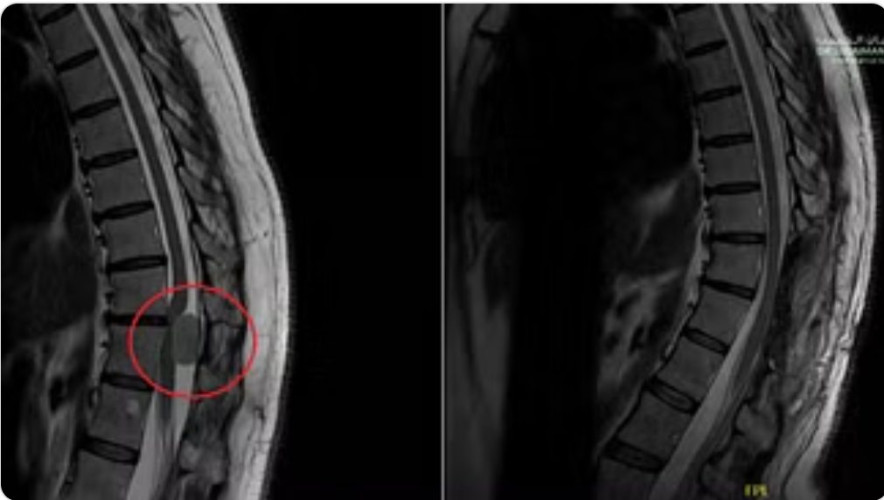

وأوضح أن المريضة وصلت للعيادة على كرسي متحرّك غير قادرة على الحركة نهائياً ، أو أداء مهامها اليومية الاعتيادية، نتيجة التأخر في التشخيص والعلاج، حيث تمّ إجراء الفحص السريري الذي أثبت أن تلك الأعراض تتعلق بأورام الحبل الشوكي، وعليه تم إخضاعها لفحوصات بالرنين المغناطيسي (M.R.I).

وقال د. النبهان؛ إن نتائج الفحوصات أبانت بدقة وجود ورم كبير في الفقرات الصدرية بالعمود الفقري بطول 3 سم، وضاغط بشدة على النخاع الشوكي مسبّباً الأعراض السابق ذكرها، الأمر الذي استدعى التدخل الجراحي العاجل، مشيراً إلى أنه عقب دراسة الفريق الطبي لنتائج الفحوصات، تمّ إطلاع المريضة على الخطة العلاجية.